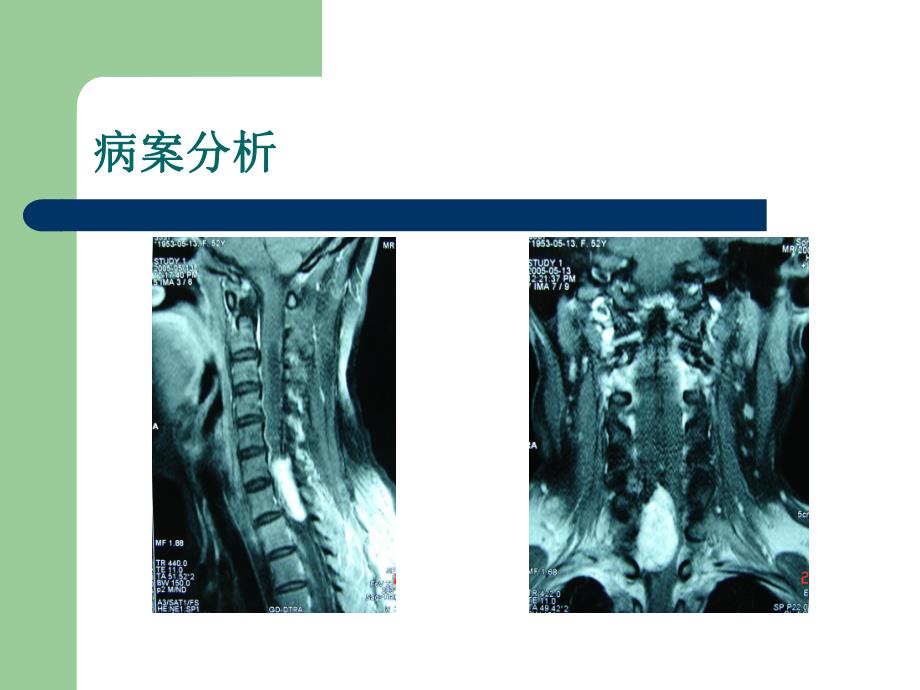

2、血及呼吸困难,偶有盗汗,饮食睡眠尚可,精神正常。饮食睡眠尚可,精神正常。提问提问1.需进一步作何检查能明确诊断以及诊断是什么?需进一步作何检查能明确诊断以及诊断是什么?2.治疗治疗方案是什么?方案是什么?病案分析病案分析病例分析病例分析3.C68椎管内MRI显示 (1)单发)单发 (2)位于髓外)位于髓外 (3)脊髓受压明显)脊髓受压明显 (4)有明显占位效应)有明显占位效应 4.初步诊断为初步诊断为C68椎管内占位,进一步明确,进一步明确需要行手术明确病检。需要行手术明确病检。5.治疗方式?手术切除肿瘤,病检为神经鞘留治疗方式?手术切除肿瘤,病检为神经鞘留发病率发病率 椎管内神经鞘瘤是椎管内